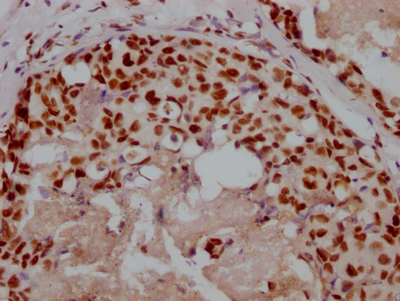

圖片:

應(yīng)用范圍:ELISA, IHC

Application Recommended Dilution IHC 1:20-1:200 -